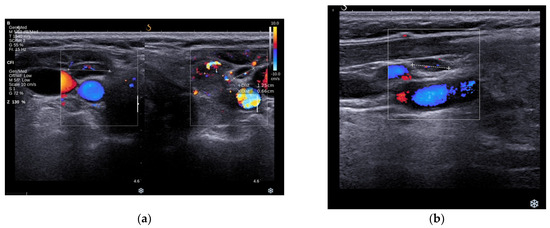

3.2.2. Thyroid Ultrasound

3.3.2. Thyroid Ultrasound